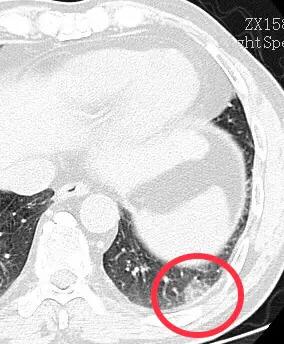

1.一过性磨玻璃结节

一过性磨玻璃结节就是指一开始肺部ct发现有磨玻璃结节,但是经过消炎吃药之后,磨玻璃结节消失了。相信很多朋友都有这种经历。这种磨玻璃结节,称之为一过性磨玻璃结节,都是细菌感染引起的。通过治疗之后都是可以完全治愈的。